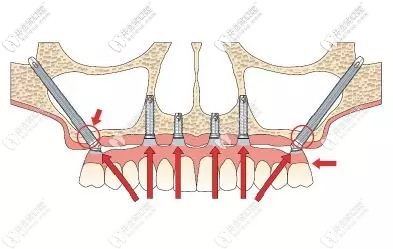

面對(duì)這種情況,想要做種植牙就要進(jìn)行穿顴種植,首先要了解顧客的身體情況;為了確保手術(shù)的能成功,需要制作3D打印頜骨模型,然后數(shù)碼設(shè)計(jì)術(shù)前導(dǎo)板......

術(shù)中,植體一段穿過(guò)顴骨另一端平放置在盡可能接近牙槽嵴頂?shù)奈恢?,且種植體有一個(gè)45°的轉(zhuǎn)角基臺(tái),就算在頜骨極度缺失的情況下,不植骨也可以馬上種植即刻修復(fù)哦!

穿翼種植牙示意圖